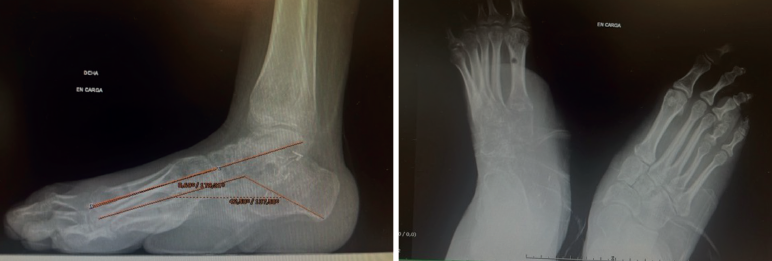

Tras la retirada del fijador y la inmovilización, se autorizó la carga. La paciente presenta un pie plantígrado e indoloro sin complicaciones asociadas (Figura 4).

Además, se observa una normalización del ángulo de Meary y el de Costa-Bartani (Figura 5).

El valor normal del ángulo de Meary sería menor de 10° y nos sirve para evaluar la alineación del arco longitudinal medial del pie y cuantificar deformidades sagitales(11).

El valor normal del Costa-Bartani es entre 120 y 130°, y evalúa la altura y la estabilidad del arco medial, y el equilibrio estructural del pie(12).

Al año de la cirugía, la paciente se encuentra deambulando de manera autónoma y sin ayudas, con un buen resultado global a nivel clínico y radiológico.